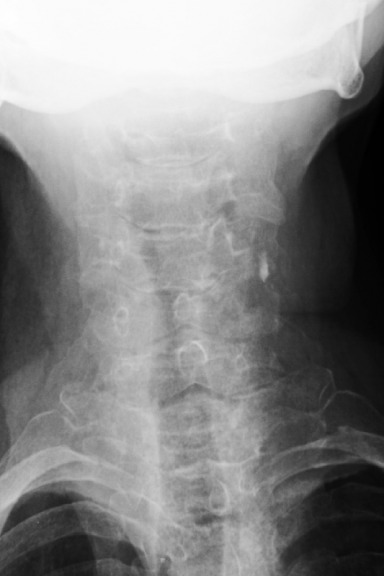

1. What is the key finding?

There are obvious degenerative changes of the cervical spine as well as osteopenia. The key finding however is the posterior subluxation of the atlas (C1) on the axis (C2). This is evident by the disruption of the spinolaminar line. The opacity with the sclerotic borders in the expected location of the dens represents the anterior arch of C1. Posterior to that you can make out the subtle appearance of a rounded opacity representing the dens, displaced posteriorly from the body of C2.

Diagnosis - Unstable Os Odontoideum